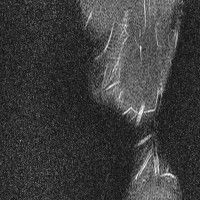

무릎 mri 간단히 봐주실 수 있으시나요 ㅠㅠ

안녕하세요 8년전 십자인대 수술하고 최근 무리한 운동에 무릎 불편감이 생겨서

mri 찍었습니다.

진단결과는 첫 찍은 병원에서 활액막염 이라는 진단을 받았습니다. 혹시 봐주실 수 있으실까요?

올라온 MRI가 단편적이라서 정확한 진단에 어려움이 있지만 십자인대에는 큰 이상이 있지는 않은것 같으며, 무릎관절내 물이 있는 것으로 보아 활액막염의 진단이 맞을 것 같습니다.

하지만 단편적인 영상이기 때문에 촬영병원에서 정확한 판독지 등을 받으시는 것이 좋겠습니다.